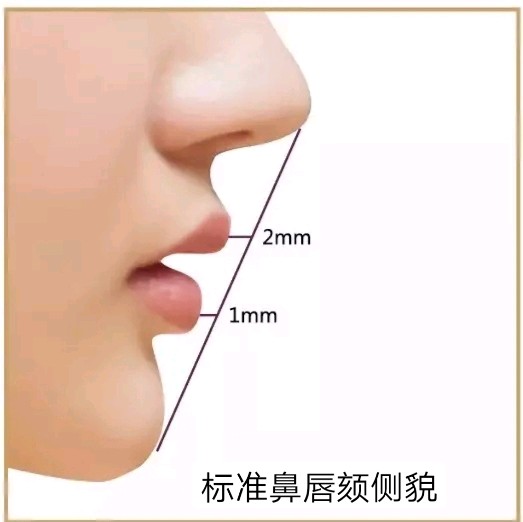

颏部(俗称下巴)作为颜面结构之一是鼻唇颏关系协调的基础,而鼻唇颏关系的协调是容貌美的重要标志;颏部是面部审美的重要标志之一。